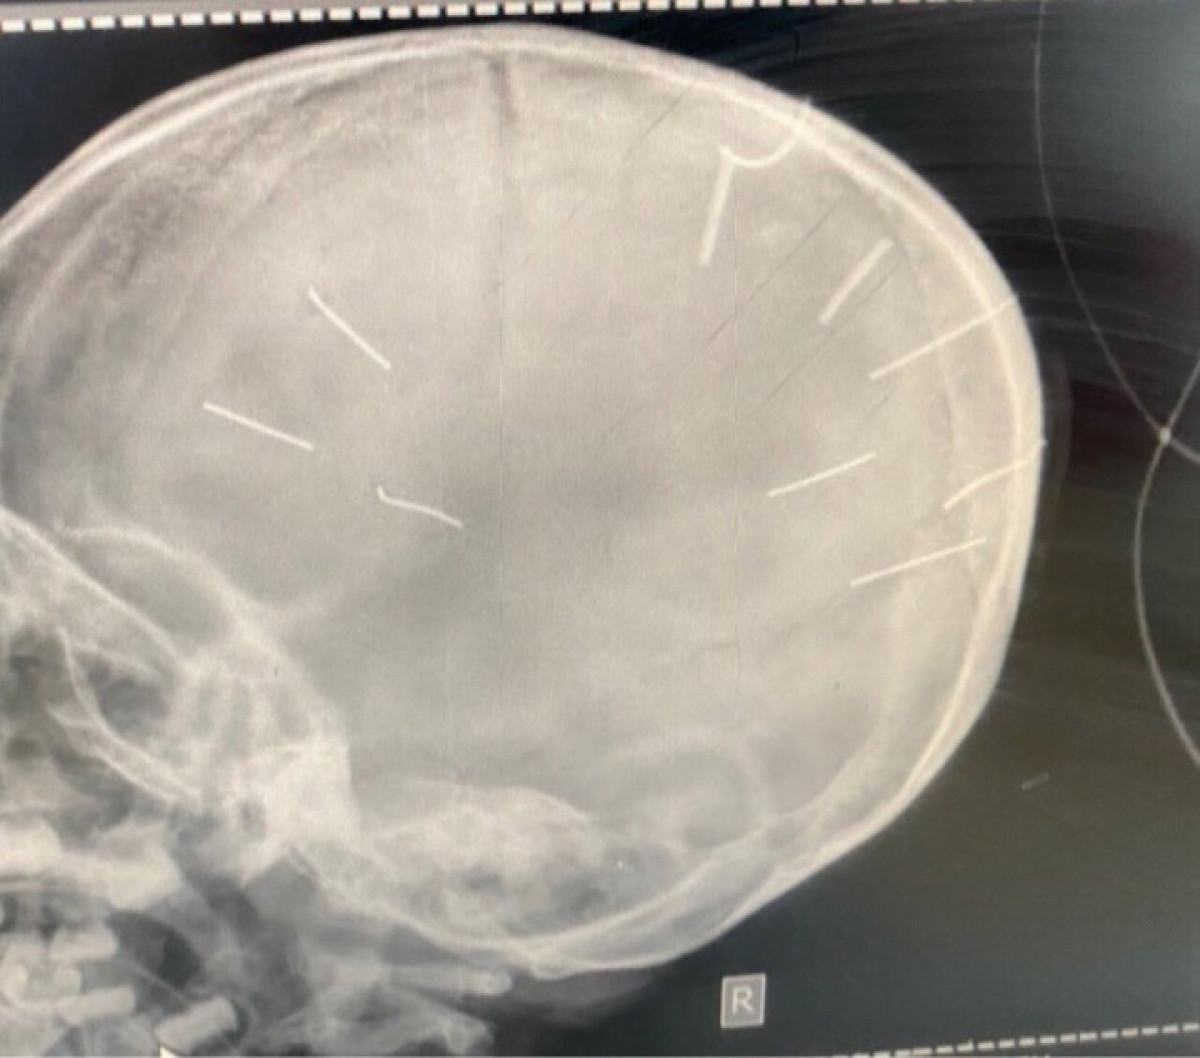

| Theo Công an huyện Thạch Thất, đối tượng Nguyễn Trung Huyên là người đã đóng 9 chiếc đinh vào đầu bé Đ.N.A. Hiện toàn bộ hồ sơ vụ việc đã được Công an huyện Thạch Thất chuyển lên Công an TP Hà Nội. |